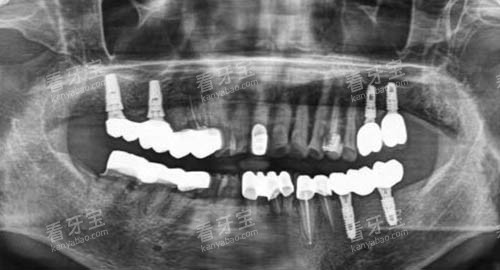

种植牙项目凭借小创口、长效、仿真度高、咀嚼功能修复好的优势,收获了众多中老年市民的认可。机构采用进口种植体,结合小创口种植技术,种植过程中创伤小、出血少、痛感轻,无需住院,术后修复快,不损伤邻牙,种植后的牙齿与天然牙齿几乎无差别。

治疗前,医生会通过口腔CT精密检测牙槽骨状况,制定个性化种植方案;术后提供可靠的护理指导与跟进服务,助力种植体更好地与牙槽骨结合,延长使用寿命。相较于传统假牙,种植牙更舒适耐用,且收费亲民、价格透明,让更多中老年市民能够承担得起。